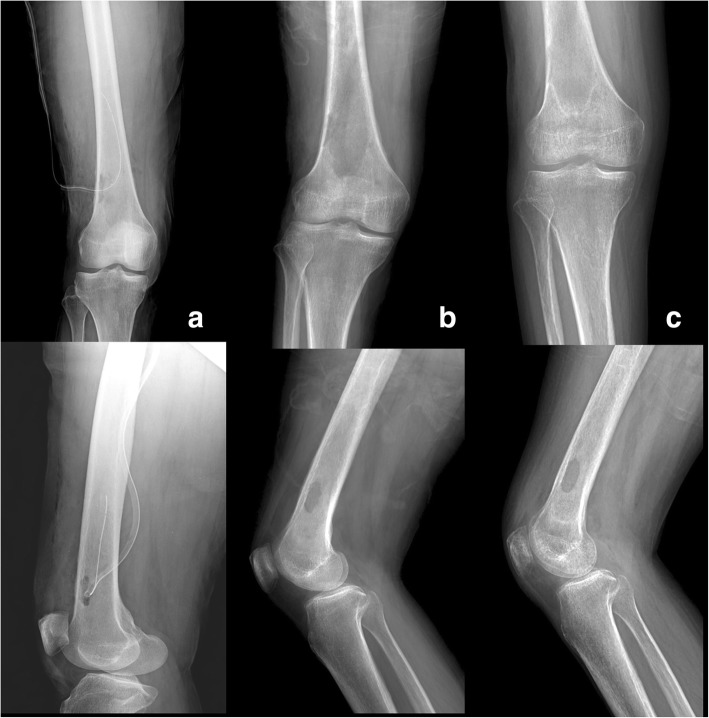

Fig. 1.

Initial X-ray findings of the right knee. Anteroposterior (a) and lateral (b) radiography of the right knee revealed multifocal osteolytic changes (arrow) in the distal metaphysis area of the right femur. There was a geographic lesion with an irregular margin, but, no sclerotic rim (Lodwick classification type 1B). There was no destruction of cortical bone. However, a subtle cortical thickening lesion suggesting solid type of periosteal reaction was found at superior aspect of lateral femoral condyle (arrow head, a)

On the physical examination, an increased local heat in the proximal area of the right knee without an external wound, or draining sinus was confirmed. Body temperature was 38.8 °C. Laboratory test results showed the following: leukocytes 7260/μL (neutrophil 79.1%), absolute neutrophil count 4050, C-reactive protein (CRP) 21.26 mg/L, and erythrocyte sedimentation rate (ESR) 72 mm/h. We conducted synovial fluid analysis on the fluid extracted from the right knee joint. Synovial fluid analysis revealed a white blood cell count of 870/mm3, a polymorphonuclear leukocyte of 45%, and no crystals were found. Anteroposterior and lateral radiography of the right knee revealed multifocal osteolytic changes in the distal metaphysis area of the right femur. The lesion had an irregular margin but no sclerotic rim (Lodwick classification type 1B). There was no definite destruction of cortical bone. However, a subtle cortical thickening lesion suggesting solid type of periosteal reaction was found at superior aspect of lateral femoral condyle (arrow head, a) (Fig. 1). The axial (a), coronal (b), and sagittal (c) T2-weighted magnetic resonance imaging (MRI) of the right knee, which were previously performed at another hospital (with lacking information of T1 weighted and enhanced image), are shown in Fig. 2. Multifocal intraosseous lesions (6.1 × 2 × 2 cm) at metaphysis and diaphysis of the distal femur were observed with no destruction of cortical bone. However, double-contour periosteal line, which suggesting periosteal reaction (arrow head, A and B) at lateral aspect, and marrow edema were found in the adjacent tissues (asterisk, B). Considering the patient’s age, location of the lesion, margin, and absence of cortical destruction, we suspected osteomyelitis rather than a bony malignancy.